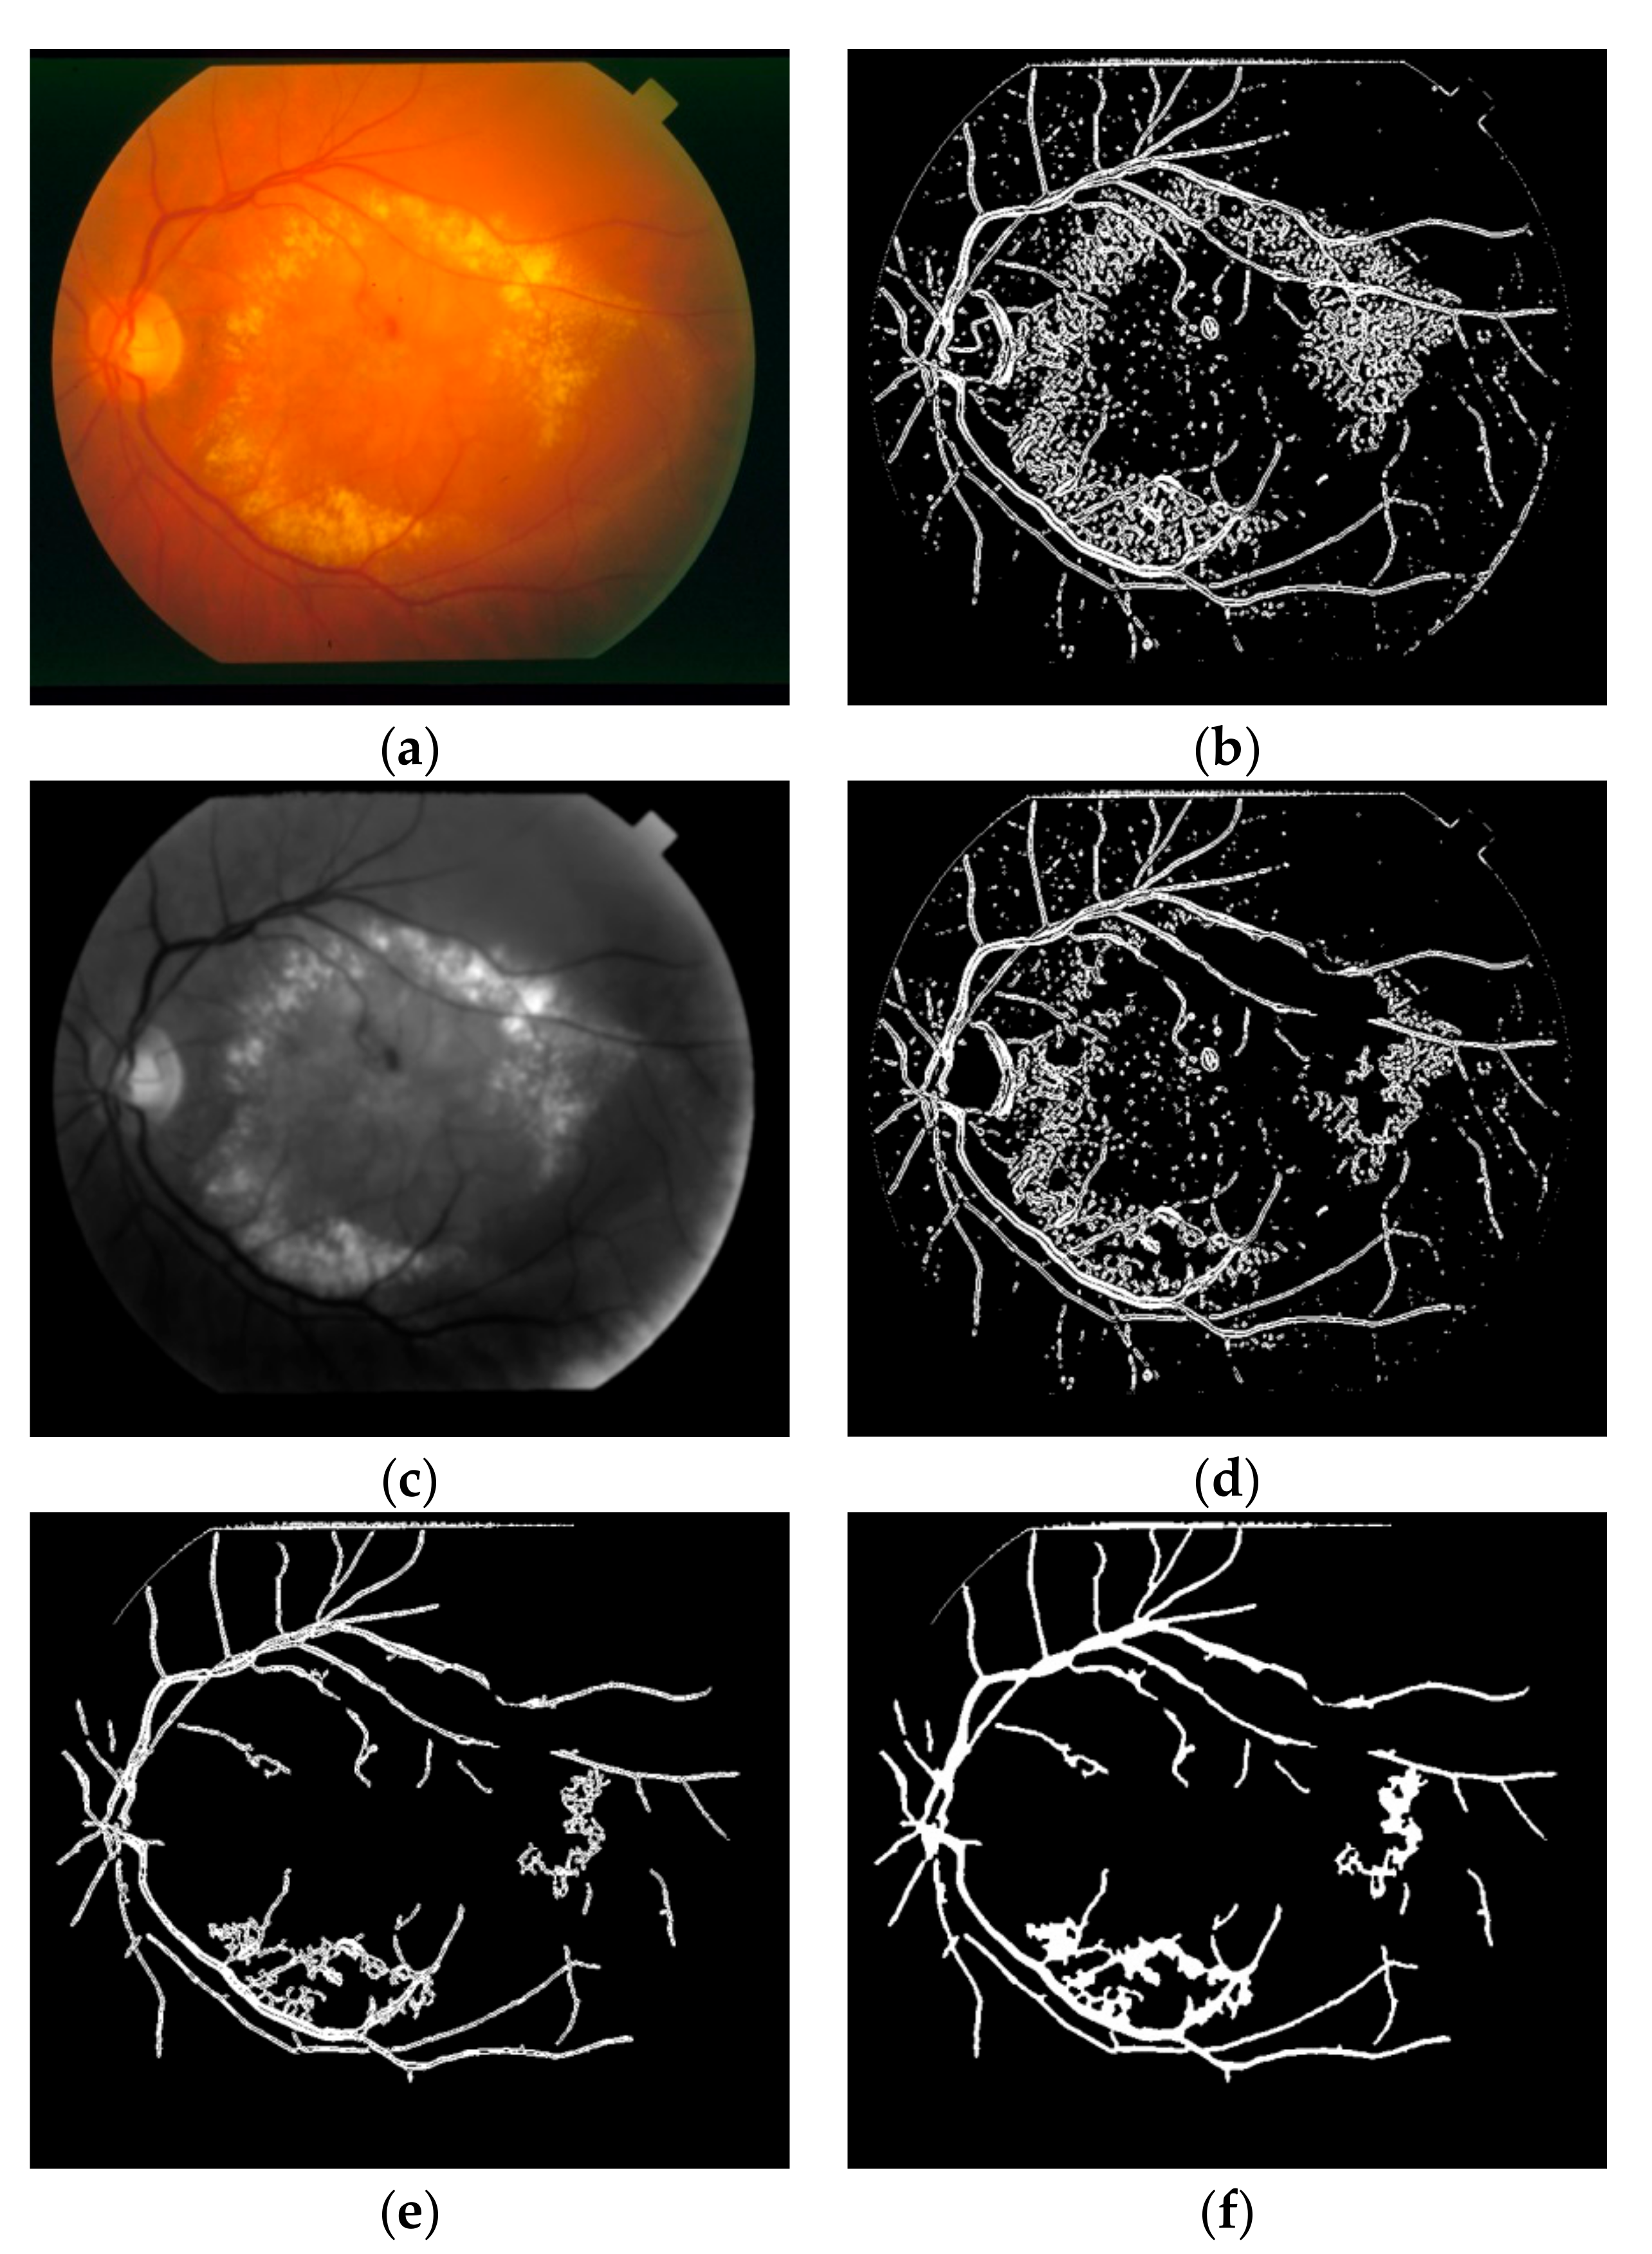

In this study, two different approaches are offered for the lesion removal procedure at the post-processing step. The effects of the post-processing procedures are shown on the segmentation steps of an image having DR in STARE dataset as in Figure 6. The first approach targets especially the spread hard and soft exudate lesions. The highest 10% of the histogram of the product of hue and green color space of the retinal image having these kinds of lesions is removed from the segmentation result as in Figure 6d.

The second approach aims to remove all the other lesions or residual artefacts by taking into account their geometric structures such as solidity and eccentricity. The ratio of the region of a connected component to its convex hull is defined as solidity. The ratio of the distance between the foci of the ellipse which has same the second-moments as a connected component and its major axis length is defined as eccentricity [44]. It was empirically inspected with a high probability that the connected components having solidity value above 0.3 and eccentricity value below 0.95 are lesion. After removing the lesion-like connected components as in Figure 6e, all the residual connected components which are smaller than 100 pixels are deleted from the segmentation result. Finally, the small holes occurring on the vessels because of the central vessel reflex are filled using some successive morphological operations as shown in Figure 6f.

Figure 6. Post-processing procedures on image 2 on STARE dataset (a) retinal image having DR; (b) first segmentation result; (c) product of hue and green colors; (d) effect of histogram-based bright lesion removal step; (e) effect of solidity and eccentricity-based lesion removal step; (f) effect of small hole filling step.